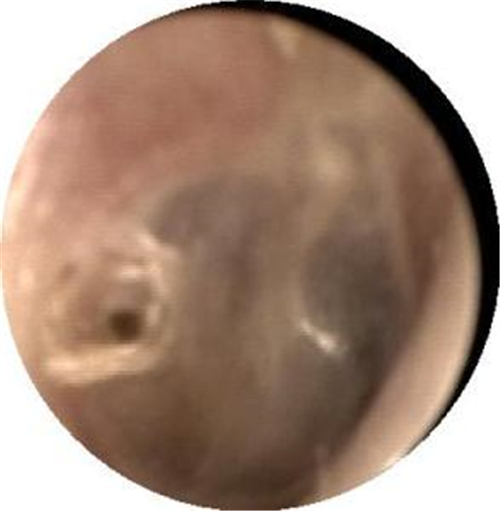

自愈的鼓膜穿孔